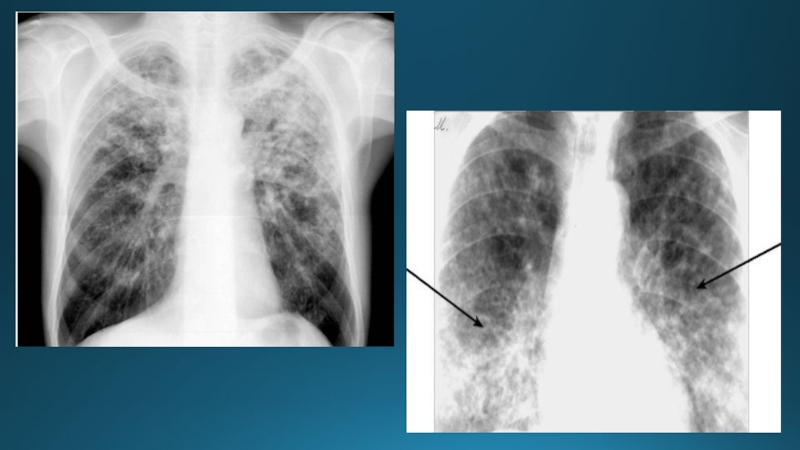

3. Диссеминация

Шектелген диссеминация

Диффузды диссеминация

Ошақты көлеңке синдромы және шектелген диссеминацияКіші дөңгелекті немесе әртүрі формалы 0,1 - 1см-ге дейінгі көлеңкені ошақ деп

Слайд 40Ошақтың орналасуы:

Бір- немесе екіжақтылы

Өкпе алаңының жоғарғы, ортаңғы немесе төмеңгі бөлігінде

Өкпе алаңдарыңдағы жайылған диссеминация ошақтары

Ошақтың мөлшері:

Милиарлы (1-2мм)

Ұсақ

(3-4мм)

Орташа (5-8мм)

Ірі (9-12мм)